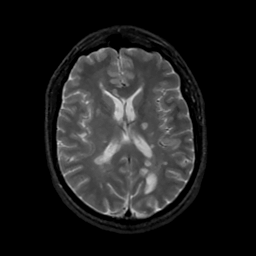

MR Study #16, June 23, 1991 -- Slice #29

[Home][Help][Clinical][Tour 1][Tour 2] Slice 29